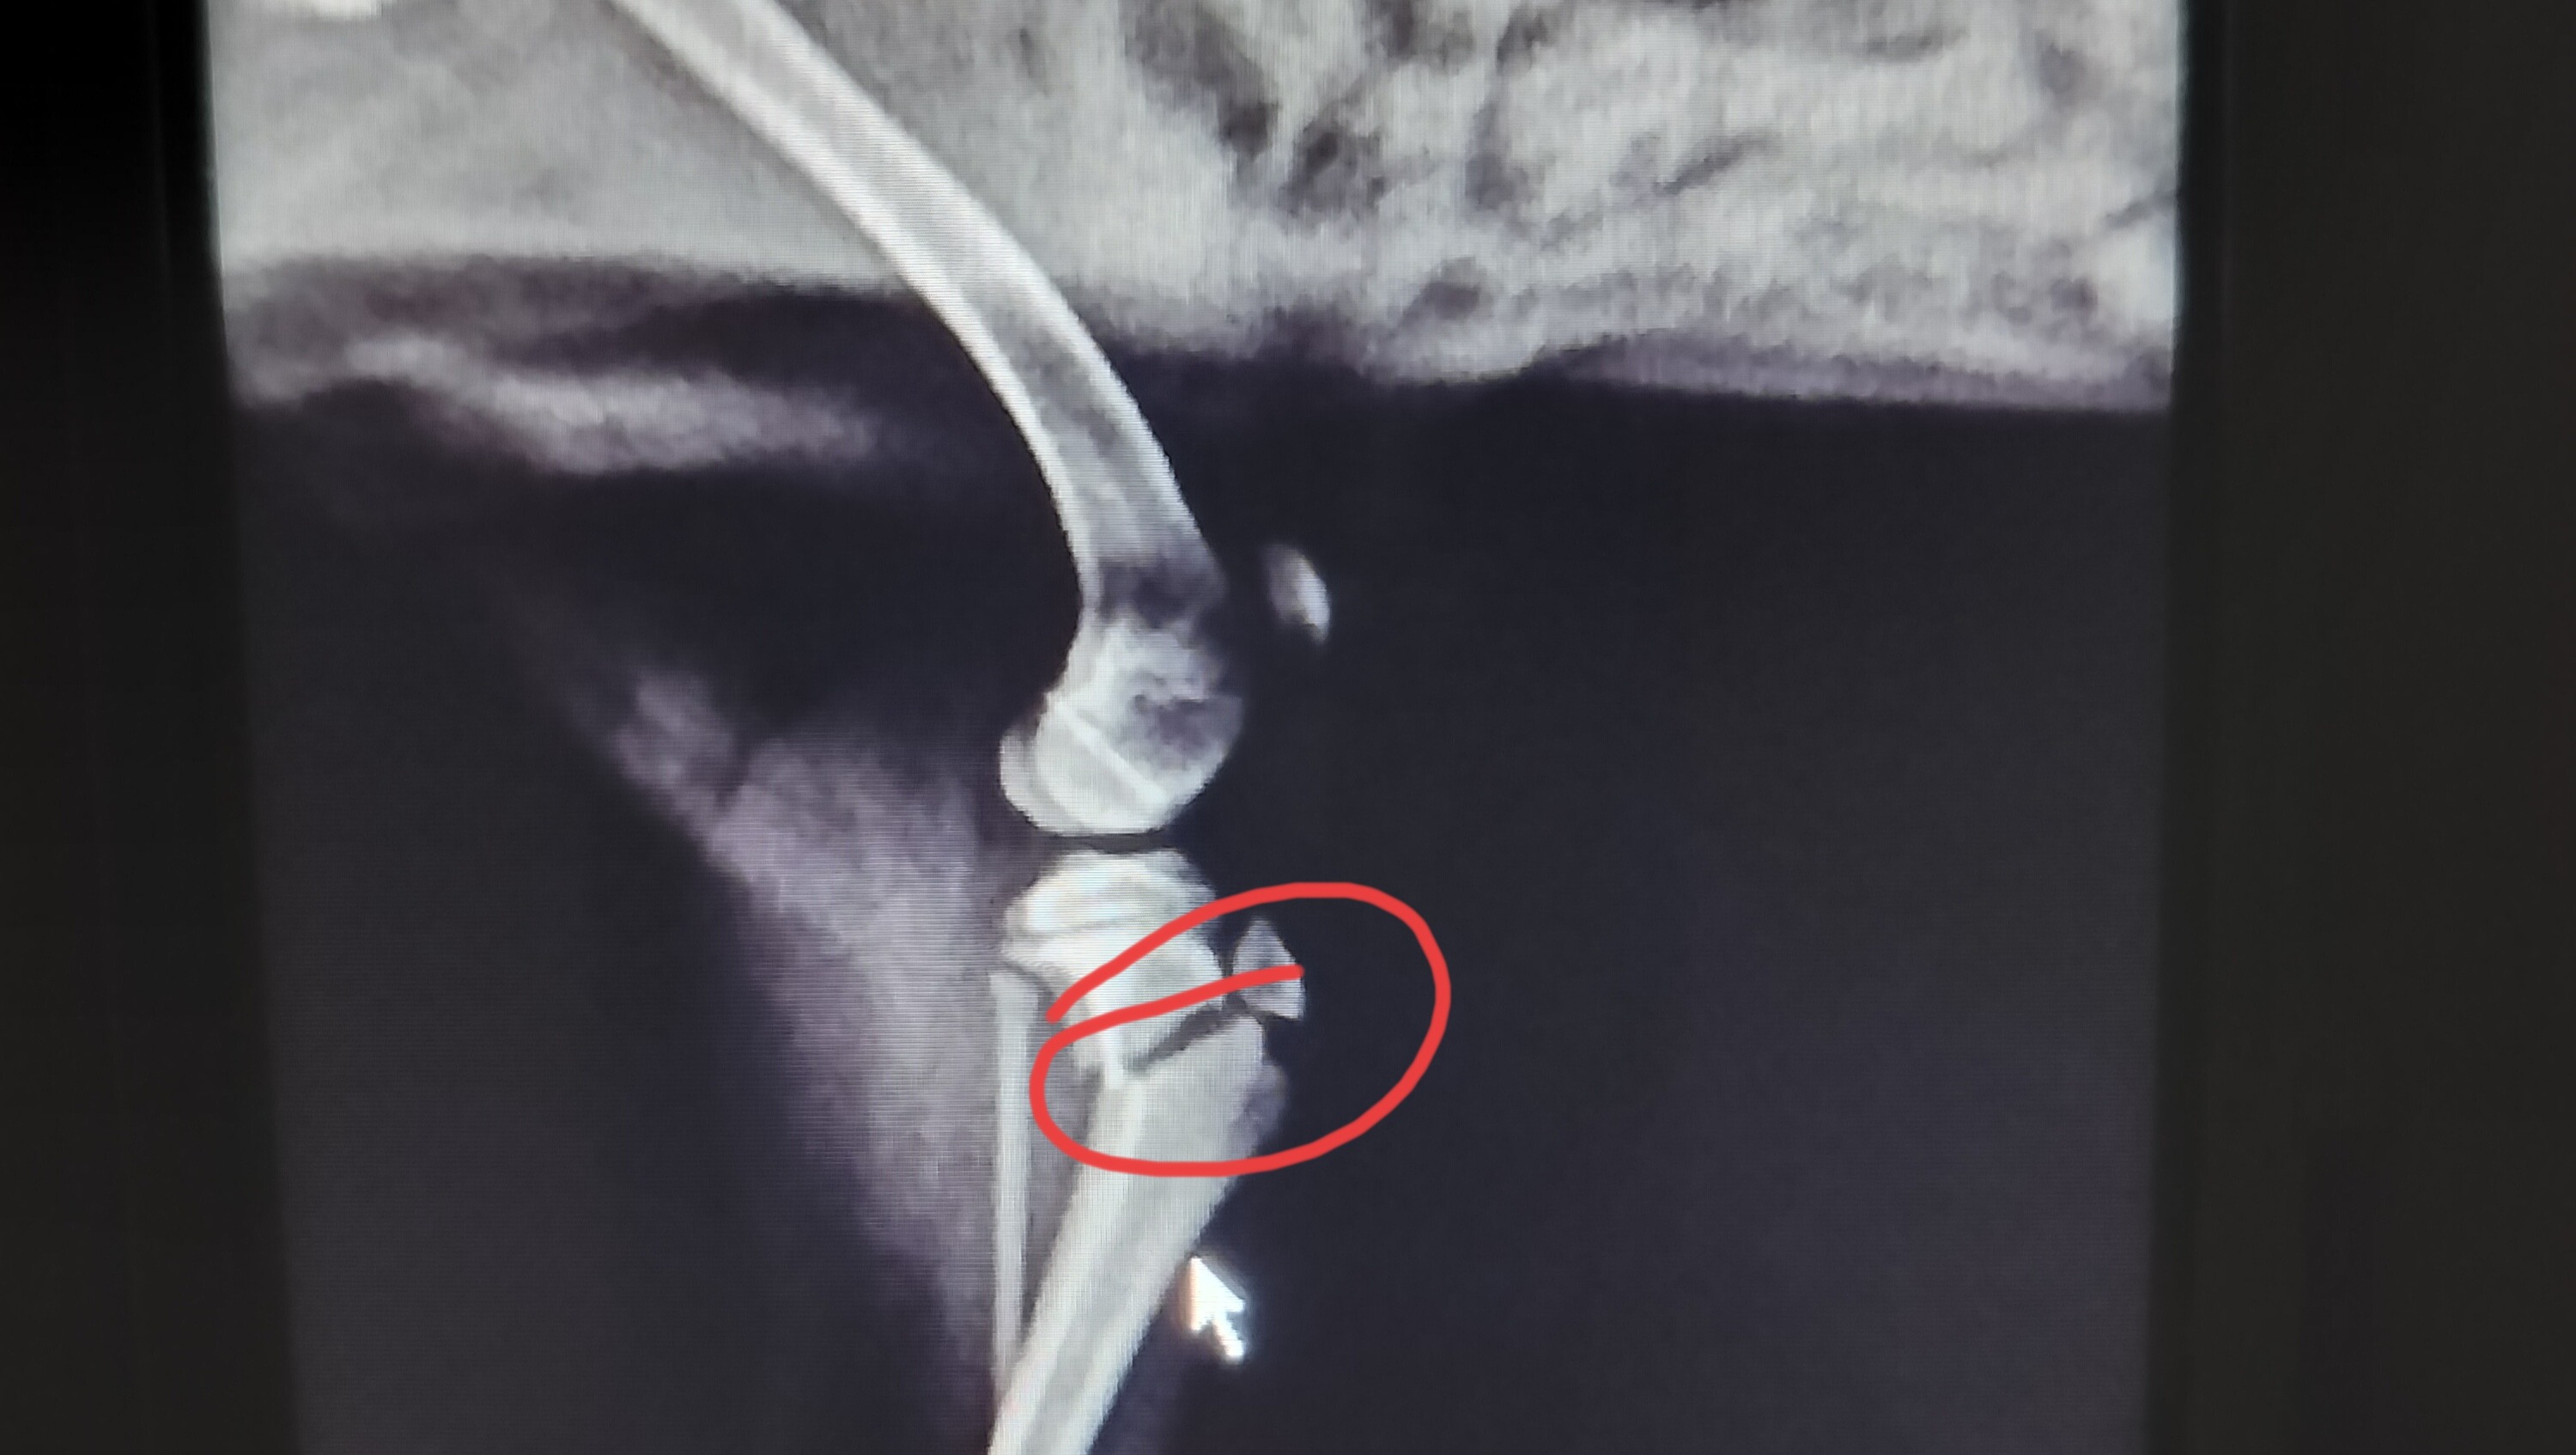

scouting the area three minutes away. Once there they immobilized his leg to avoid further damage and as you can see he has a big fracture and the only explanation might be that he fell from the stairs because he was left out. I am angry, frustrated, in disbelief because I trusted and I shouldn't. I feel like a failed in protecting my furbaby.

The vets office I went to isn't equipped with much and they did what they could and told me to take him to orthopedic surgeon which I did today February 8, 2024. The estimate is included.